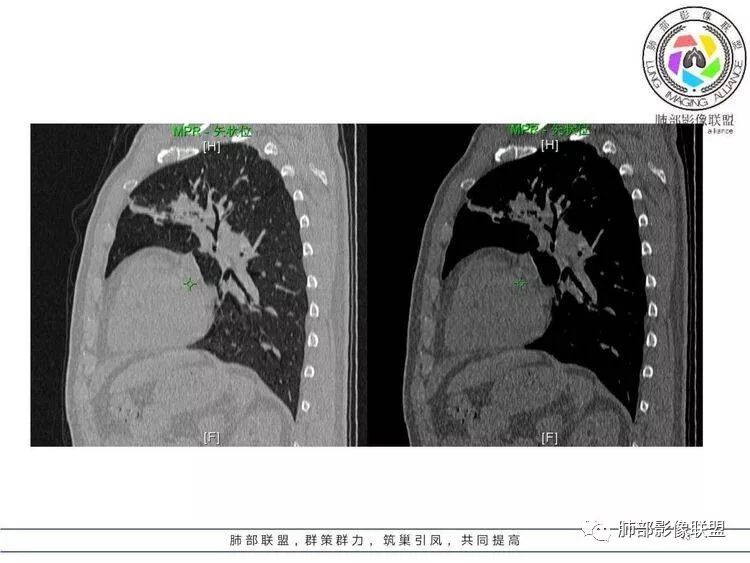

王秀仙:左肺上叶肿块,边缘平直收缩,周围可见长索条,轻度强化,密度不均可见低密度坏死,考虑结核。鉴别腺癌。Yiren  Sishui(厶水伊人):晨读:左肺上叶肿块,近胸膜侧光滑,提示符合淋巴回流病变,周围条索,符合肉芽肿性病变,环形强化,中心坏死,考虑结核可能luys:左肺上叶病变,沿支气管分布,边缘平直收缩,周围见长索条,轻度强化,伴边界可见低密度坏死灶。考虑特殊感染。灶内支气管中断,临床以咯血就诊,鉴别肿瘤。博麟:左上胸廓稍缩小,长条索病灶,冠状位似见支气管截断,坏死边界似乎欠清,猜个纤维条索基础上合并瘢痕癌红日东升:晨读:左上叶结块,前缘有粗大索条向前延伸,邻近前联合线明显左移,提示收缩明显。结块边缘平直、收缩;增强结块及索条明显强化,内血管走行自然,坏死灶周围似见三层结构;考虑炎性病变。wonderful:肿块实性边缘光滑  考虑良性病变 合并咯血 。结核或曲霉玫:左肺上叶不规则形软组织密度肿块影,边界清晰,期内密度不均匀,可见坏死,病灶向前呈条索状延伸,矢状位病灶形态欠规整,似有血管中断,考虑恶性病变可能,待除外结核?张帅:左肺上叶病变,病变周围平直,长毛刺,病灶内可见低密度区及支气管征,矢状位提示前段阻塞,病灶内气管不规则扩张,病灶周围有卫星灶,考虑良性病变:结核?我心飞翔:病灶边缘平直,中央可见坏死,周围磨玻璃边界欠清,考虑炎性病变张延军:左肺上叶尖后段肿块,边缘以平直为主,局部膨隆,内见片状坏死区,边界欠清,相应尖后段支气管闭塞,考虑占位并不张,腺癌?建议抗炎治疗后复查丽:左肺上叶病变,边缘平直,并可见长索条,增强后密度不均,可见坏死,首先考虑结核,但重建后支气管走形欠连续,似有截断,恶性待排毛勤香:左肺上叶病灶,边缘平直为主,周围索片影,增强强化不均匀,内有坏死,重建支气管走行欠规则,似有截断,老年男性,需排除恶性(鳞癌?)并阻塞性肺炎可能王萍:左肺上叶团片,大部分边缘平直、凹陷,周围见少许条片模糊影,增强内见坏死区,余区域较均质,其内支气管部分通畅,部分变窄。咯血病史,无发热,考虑肉芽肿性炎可能性大,结核或放线菌等,肿瘤待排THINKER:左上叶,占位,围绕尖后段支气管,U型凹丶平直,长索条,有轻强化及低密度,考虑良性的,首选OP,老年不发热丶咯血,鉴鳞癌、TB飞鹰行动:左肺病灶,有明显的收缩表现,增强后病灶内部可见低密度无强化区,病灶内支气管轻度扩张呈串珠状改变,支持炎性病变,结核可能性大。杨泽锋:支持炎性病变伴小脓腔形成,但不支持结核,因为病灶内可以可见血管影THINKER:问一下各位老师:这个给的强化,是肺动末期丶主动脉未期`延迟期?大雄:老年男性,左肺上叶前段条片状实变影伴周围长条索,境界清晰,边缘部分锐利光滑、部分毛糙,增强可见中央局部坏死,周围无强化区轻中度均匀强化,无钙化,无明显卫星灶,无胸膜明显牵拉凹陷。病灶整体收缩力有,张力不明显,肿瘤概率小。临床无明显急性感染症状,倾向于慢性增生性炎症,累及段支气管,引起了咯血。结核多见,但慢性结核肉芽肿一般强化没这么明显。OP不除外。老年男性如果有长期吸烟史,鳞癌不能完全排除,鳞癌的坏死强化都符合,鳞癌收缩力也不强,形态更是变化无常左手:老年男性,咯血,左肺上叶长条样结节,边缘见牵拉影,支气管堵塞,病灶内见坏死,坏死边缘偏清,考虑鳞癌,鉴别结核宇宙星空:支持恶性。鳞癌可能性大。支气管截断及空泡征

Shelia:考虑机化性肺炎伴小脓肿形成?炎性肌纤维母细胞瘤?鉴别癌食客:左肺上叶病灶,边缘平直,周围条片影,增强内见坏死区,内支气管部分通畅,咯血病史,无发热,考虑结核,肿瘤不除外。管洪林:左肺上叶尖后段病变,整体边缘平直,部分稍收缩,临近长索条影,胸膜缘可见轻度牵拉,增强后整体强化明显,其内可见低密度类圆形坏死区,边界清,首先考虑op并小脓肿形成,但部分层面显示小支气管受阻,是否层面原因?管洪林:若是支气管阻塞,鳞癌作为鉴别雪上一枝蒿(陈显静):他这个动脉期是不是不是很明显啊,觉得跟静脉期差不多,强化值也不好分辨?徐超:左肺上叶实变,边缘平直,周围无磨玻璃及卫星灶,病灶内坏死,强化后边界清楚,无壁结节,余病灶轻中度均匀强化(对比肌肉),增强后血管显影清楚自然,未见破坏边缘毛糙,血管旁条形无强化区(粘液?)整体符合炎性特点,炎性假瘤或op可能,伴小脓肿;结核放后面待排(结核病灶内血管完好,边缘清楚,且强化近中度,不是很合理,肉芽肿到也可以)。红日东升:平扫和强化窗宽窗位不一样良孑:左上实变,有平直及长毛刺,其内支气管牵拉性扩张,提示收缩力较强,无卫星灶,强化不支持TB,均匀强化,无分叶不支持鳞癌,影像上提示慢性进程,考虑OP并脓肿,鉴别炎肌母。

1.外观呈三角形,尤其是锐三角形的病灶,一般是最不支持肿瘤的。

2.小病灶影像上观察到液化坏死一般不支持肿瘤。

3.腔内壁太规则一般不支持肿瘤。

4.炎性分泌物可以形成一定程度堵塞,但很少截断支气管。

5.结核可以强化不显著,但病灶不靠边,没有卫星灶,似乎支持点不多。